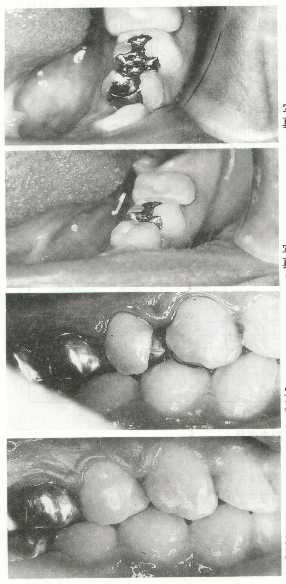

ま と め

CRインレーの臨床応用については、まず審美性を重点と考え、上下小臼歯で近心隣接面窩洞を含む形成を中心とした。昭和63年末より、応用を始めた。術前に患者に説明してから形成、装着をした所、すべての患者より満足感を示された。

まだ脱落破折はみられていないが、これから数年様子を観ていかなければならない。臨床例数は当所考えていたより少ないことがわかった。

これは小臼歯の近心面U級窩洞に限定したためと思われる。

これから様々、臨床応用を進めて行きたいと考えている。

写真3 写真4 写真5 写真6